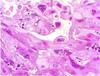

What is this disease?

Simple Bone Cyst

Also known as

1.) Solitary Bone Cyst.

2.) Traumatic Bone Cyst.

3.) Idiopathic Bone Cyst.

4.) Hemorhhagic Bone Cyst.

Remember radiographic feature

tend to Scalop between teeth

Treatment includes surgical curettage- spontaneous healing has been reported.